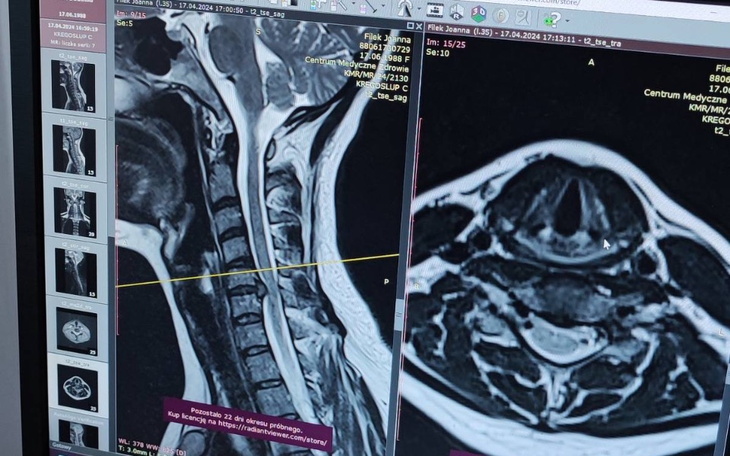

Cześć mam na imię Joanna, jestem mamą dwóch nastolatek Sam i Lili, które przez 10 lat wychowywałam sama. Na codzień zajmuje się niesieniem pomocy innym jako psycholożka i seksuolożka. Udzielam się charytatywnie w różnych fundacjach, np. dla Fundacji Wise Future University mam pod opieką nastolatka i jego rodziców. Sama robię w ramach wolontariatu telefon zaufania dla nastolatków. Od lat też przyjmuje pod swój dach podróżników z couchsurfingu. Od ponad 10 lat żyje z okropnym bólem kręgosłupa i dopiero ostatnio wysłano mnie na rezonans. Żałuję że się nie upieram bardziej, że naprawdę mnie boli a nie że wydziwiam. Okazuje się, że mam powazna przepuklinę i potrzebuje jak najszybciej operacji. Nie brakuje mi na jedzenie dla siebie i dzieci jednak mówiąc wprost na operację mnie nie stać. Kosztuje ona 25 tys złoty. I tak mogę to zrobić na NFZ, za jakieś 2 lata i to dostając nieelastyczny dysk który będzie ograniczał moją ruchomość. Ten który dostanę na jest elastyczny i będę mogła w 100% wrócić do formy, ale tego już NFZ nie pokrywa…Nie chce nikogo przekonywać żeby dał mi na tą operację pieniądze lecz jeśli uznacie, że chcecie się podzielić to z ogromną wdzięcznością przyjmę każdą złotówkę

Hello, my name is Joanna, I am the mother of two teenagers, Sam and Lili, whom I raised on my own for 10 years. On a daily basis, I helps others as a psychologist and sexologist. I volunteer in various foundations, e.g. for the Wise Future University Foundation, I take care of a teenager and his parents. I volunteer as a helpline for teenagers. I have also been welcoming couchaurfing travelers for years. I have been living with terrible back pain for over 10 years and only recently I was sent for an MRI. I wish I was more stubborn, that it really hurts me and not that I'm acting weird. It turns out that I have a serious hernia and need surgery as soon as possible. I will be honest I have enough money for food for myself and my children, but to put it bluntly, I can’t afford surgery. It costs PLN 25,000. I don't want to convince anyone to give me money for this operation, but if you decide you want to share, I will accept every penny with great gratitude.